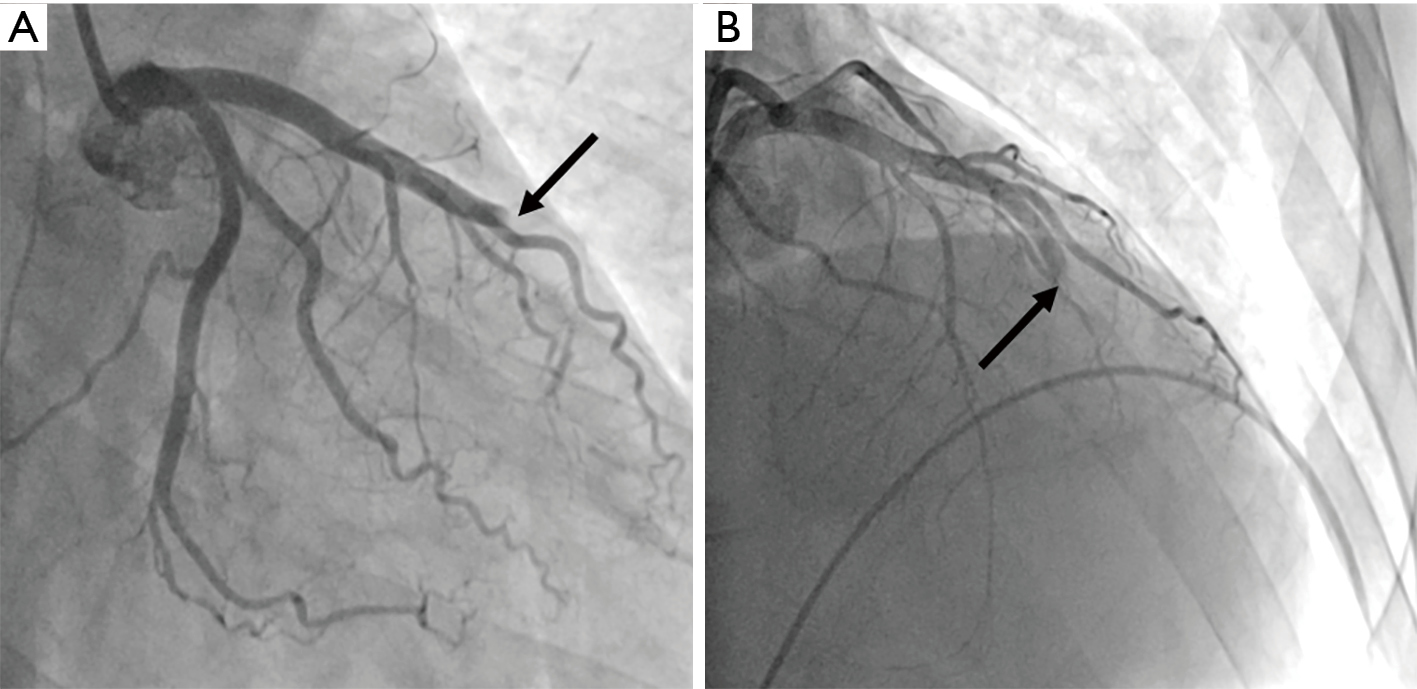

Hyperdominant Left Anterior Descending Artery Continuing As Posterior Descending Artery A Rare Coronary Artery Anomaly Cath Lab Digest

www.cathlabdigest.com